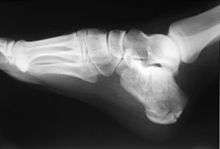

In humans, the calcaneus (/kælˈkeɪniːəs/; from the Latin calcaneus or calcaneum, meaning heel[1]) or heel bone is a bone of the tarsus of the foot which constitutes the heel. In some other animals, it is the point of the hock.

In humans, the calcaneus is the largest of the tarsal bones and the largest bone of the foot. The talus bone, calcaneus, and navicular bone are considered the proximal row of tarsal bones.[2] In the calcaneus, several important structures can be distinguished:[2]

The half of the bone closest to the heel is the calcaneal tubercle. On its lower edge on either side are its lateral and medial processes (serving as the origins of the abductor hallucis and abductor digiti minimi). The Achilles tendon is inserted into a roughened area on its superior side, the cuboid bone articulates with its anterior side, and on its superior side are three articular surfaces for the articulation with the talus bone. Between these superior articulations and the equivalents on the talus is the tarsal sinus (a canal occupied by the interosseous talocalcaneal ligament). At the upper and forepart of the medial surface of the calcaneus, below the middle talar facet, there is a horizontal eminence, the talar shelf (also sustentaculum tali), which gives attachment to the plantar calcaneonavicular (spring) ligament, tibiocalcaneal ligament, and medial talocalcaneal ligament. This eminence is concave above, and articulates with the middle calcaneal articular surface of the talus; below, it is grooved for the tendon of the flexor hallucis longus; its anterior margin gives attachment to the plantar calcaneonavicular ligament, and its medial margin to a part of the deltoid ligament of the ankle-joint.